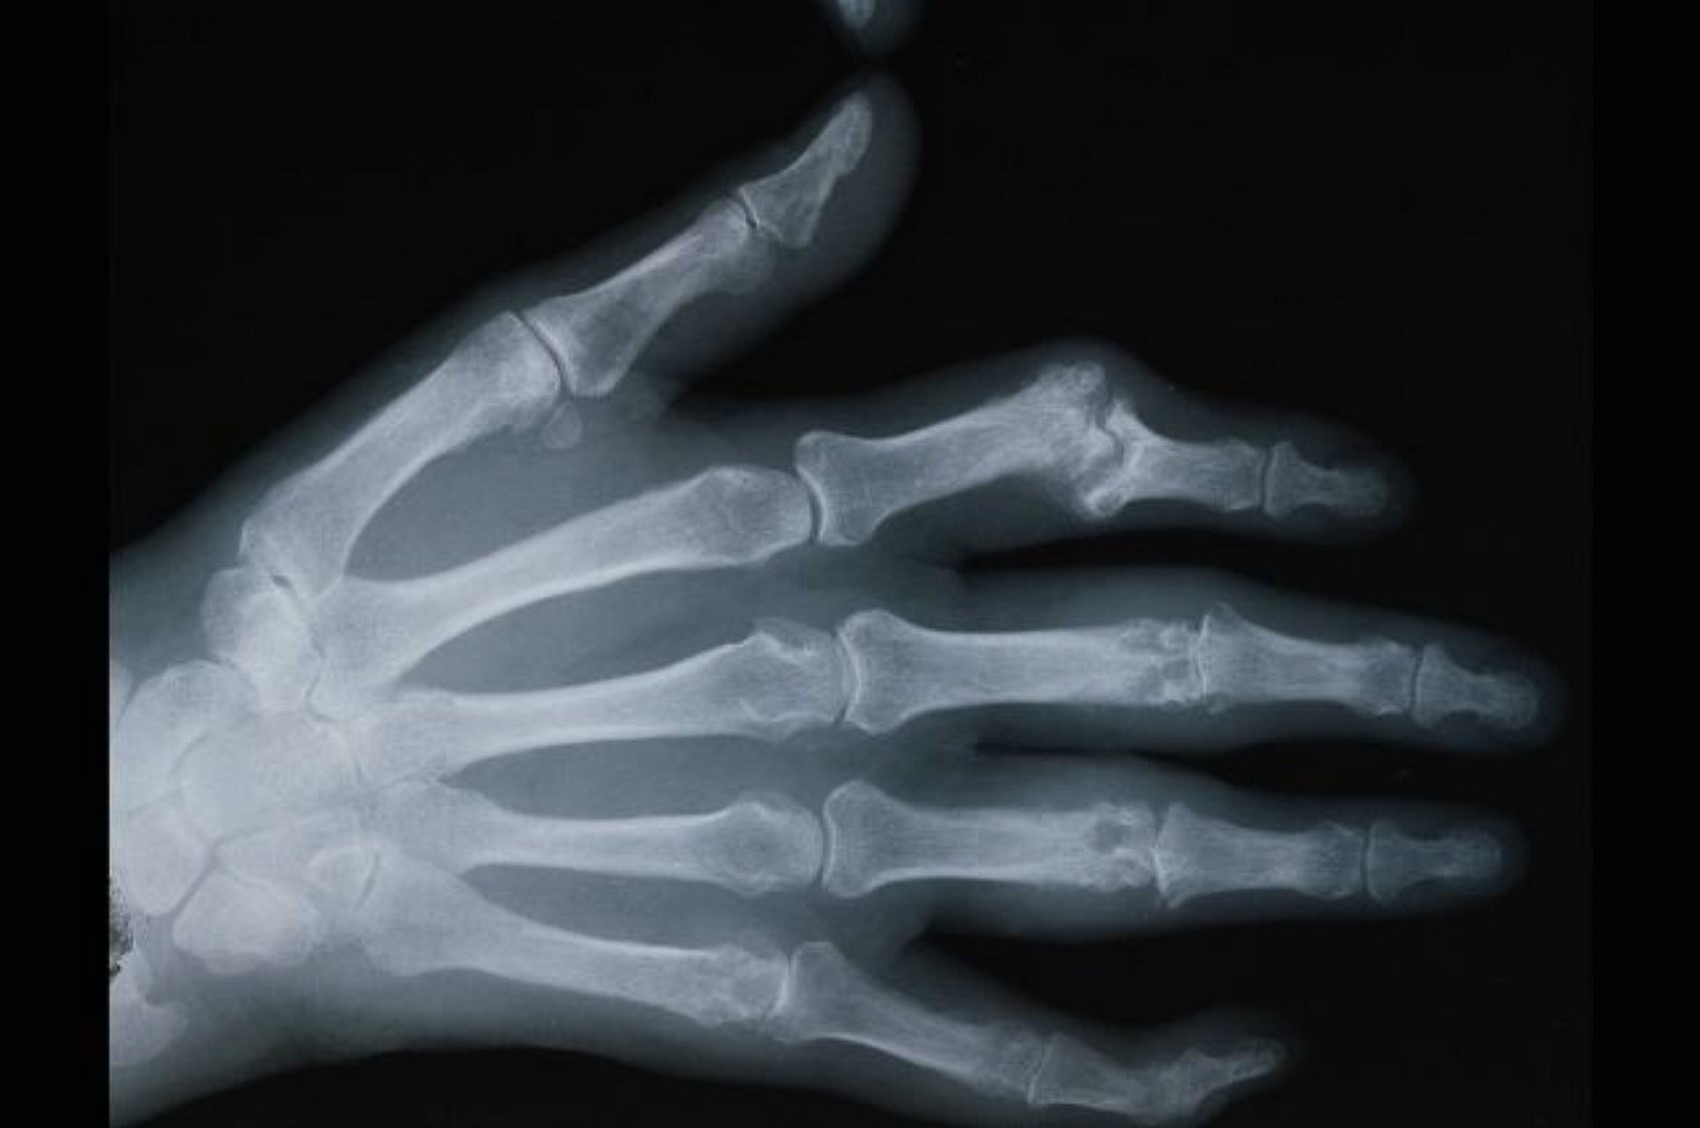

- Do you have Inflammatory Arthritis?

A team of researchers at City, University of London are aiming to explore the impact of inflammatory arthritis on planning and trying for a family, pregnancy and after pregnancy. They believe more research needs to be conducted in this area so they can better support women and their partners.